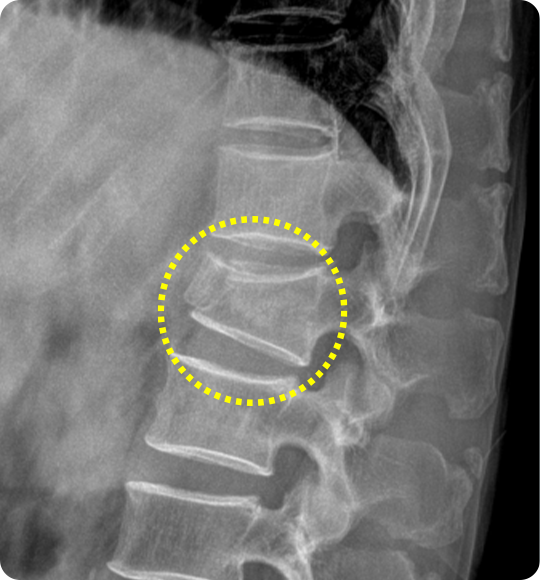

척추체 성형술 전

주저 앉은 모습

척추가 골다공증이나 외상으로 압박골절이 발생하면, 골절된 척추체가

주저앉으면서 자세 변화, 만성 통증, 추가 골절로 이어질 위험도 커집니다.

이때 골절로 약해진 척추체 내부에 특수 의료용 시멘트를 주입해 척추를 단단히

보강하고 통증을 완화하는 치료가 바로 척추체 성형술입니다.

척추 압박골절의 양상과 진행 정도에 따라 척추체 성형술과, 주저앉은 척추

높이를 일부 회복시키는 풍선 척추성형술이 적용될 수 있습니다.